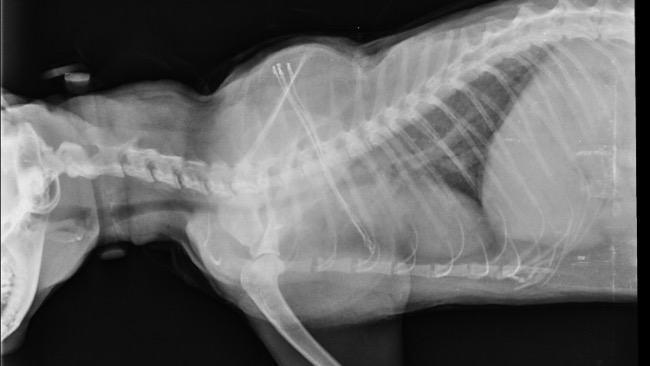

Będziemy robić dokładne zdjęcia rtg.

Florka ma płyn w opłucnej😕

Jutro o 12.30 mamy kardiologa.

Mam przeczucie, że to jednak fip😔